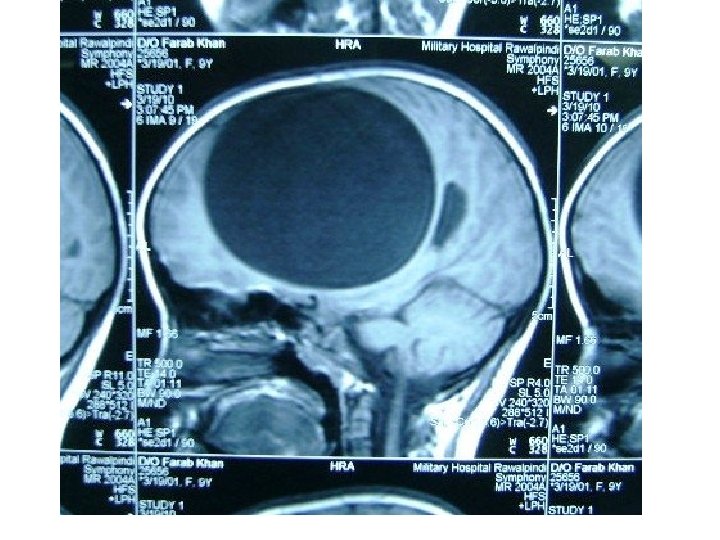

Diagnosis • large non enhancing vesicle that is well demarcated from the surrounding brain parenchyma. • Some lesions may be calcified. • epidural cysts have a biconvex shape or a multilocular appearance and may be associated with bone erosion.

Pathology • E. granulsus cysts are large, spherical, and well demarcated from surrounding tissue. • within the CNS, these cysts may be located in the brain parenchyma, ventricular system, subarachnoid space, epidural space, orbits, and both the epidural and subarachnoid spaces in the spinal canal.

CYSTIC HYDATID DISEASE OF THE BRAIN • Dowling's technique: hydrostatic expulsion of the entire cyst by irrigation of saline solution between the lesion and the surrounding nervous tissue. • The aim of this technique is to remove the cyst without damaging its walls.